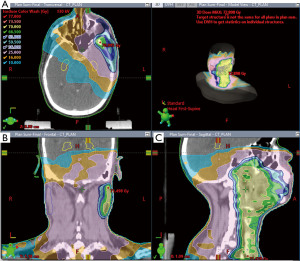

Radiotherapy planning

Planning and contouring were done using Varian Eclipse version 13.6 Treatment Planning System (TPS) (Version 8.6.17, Varian Medical System, Inc., Palo Alto, CA, USA). and dosimetric calculations were done using the anisotropic analytical algorithm (AAA). Dose evaluation to the hippocampus was done in previously planned and delivered IMRT patients, who were categorized as Group 1. Group 1 patients were then replanned by incorporating hippocampal dose constraints in the planning process, categorized as Group 2. The dosimetric parameters initially planned in Group 1 and re-planned in Group 2 patients were evaluated to determine whether the hippocampal dose constraints were achieved (Figures 2,3).